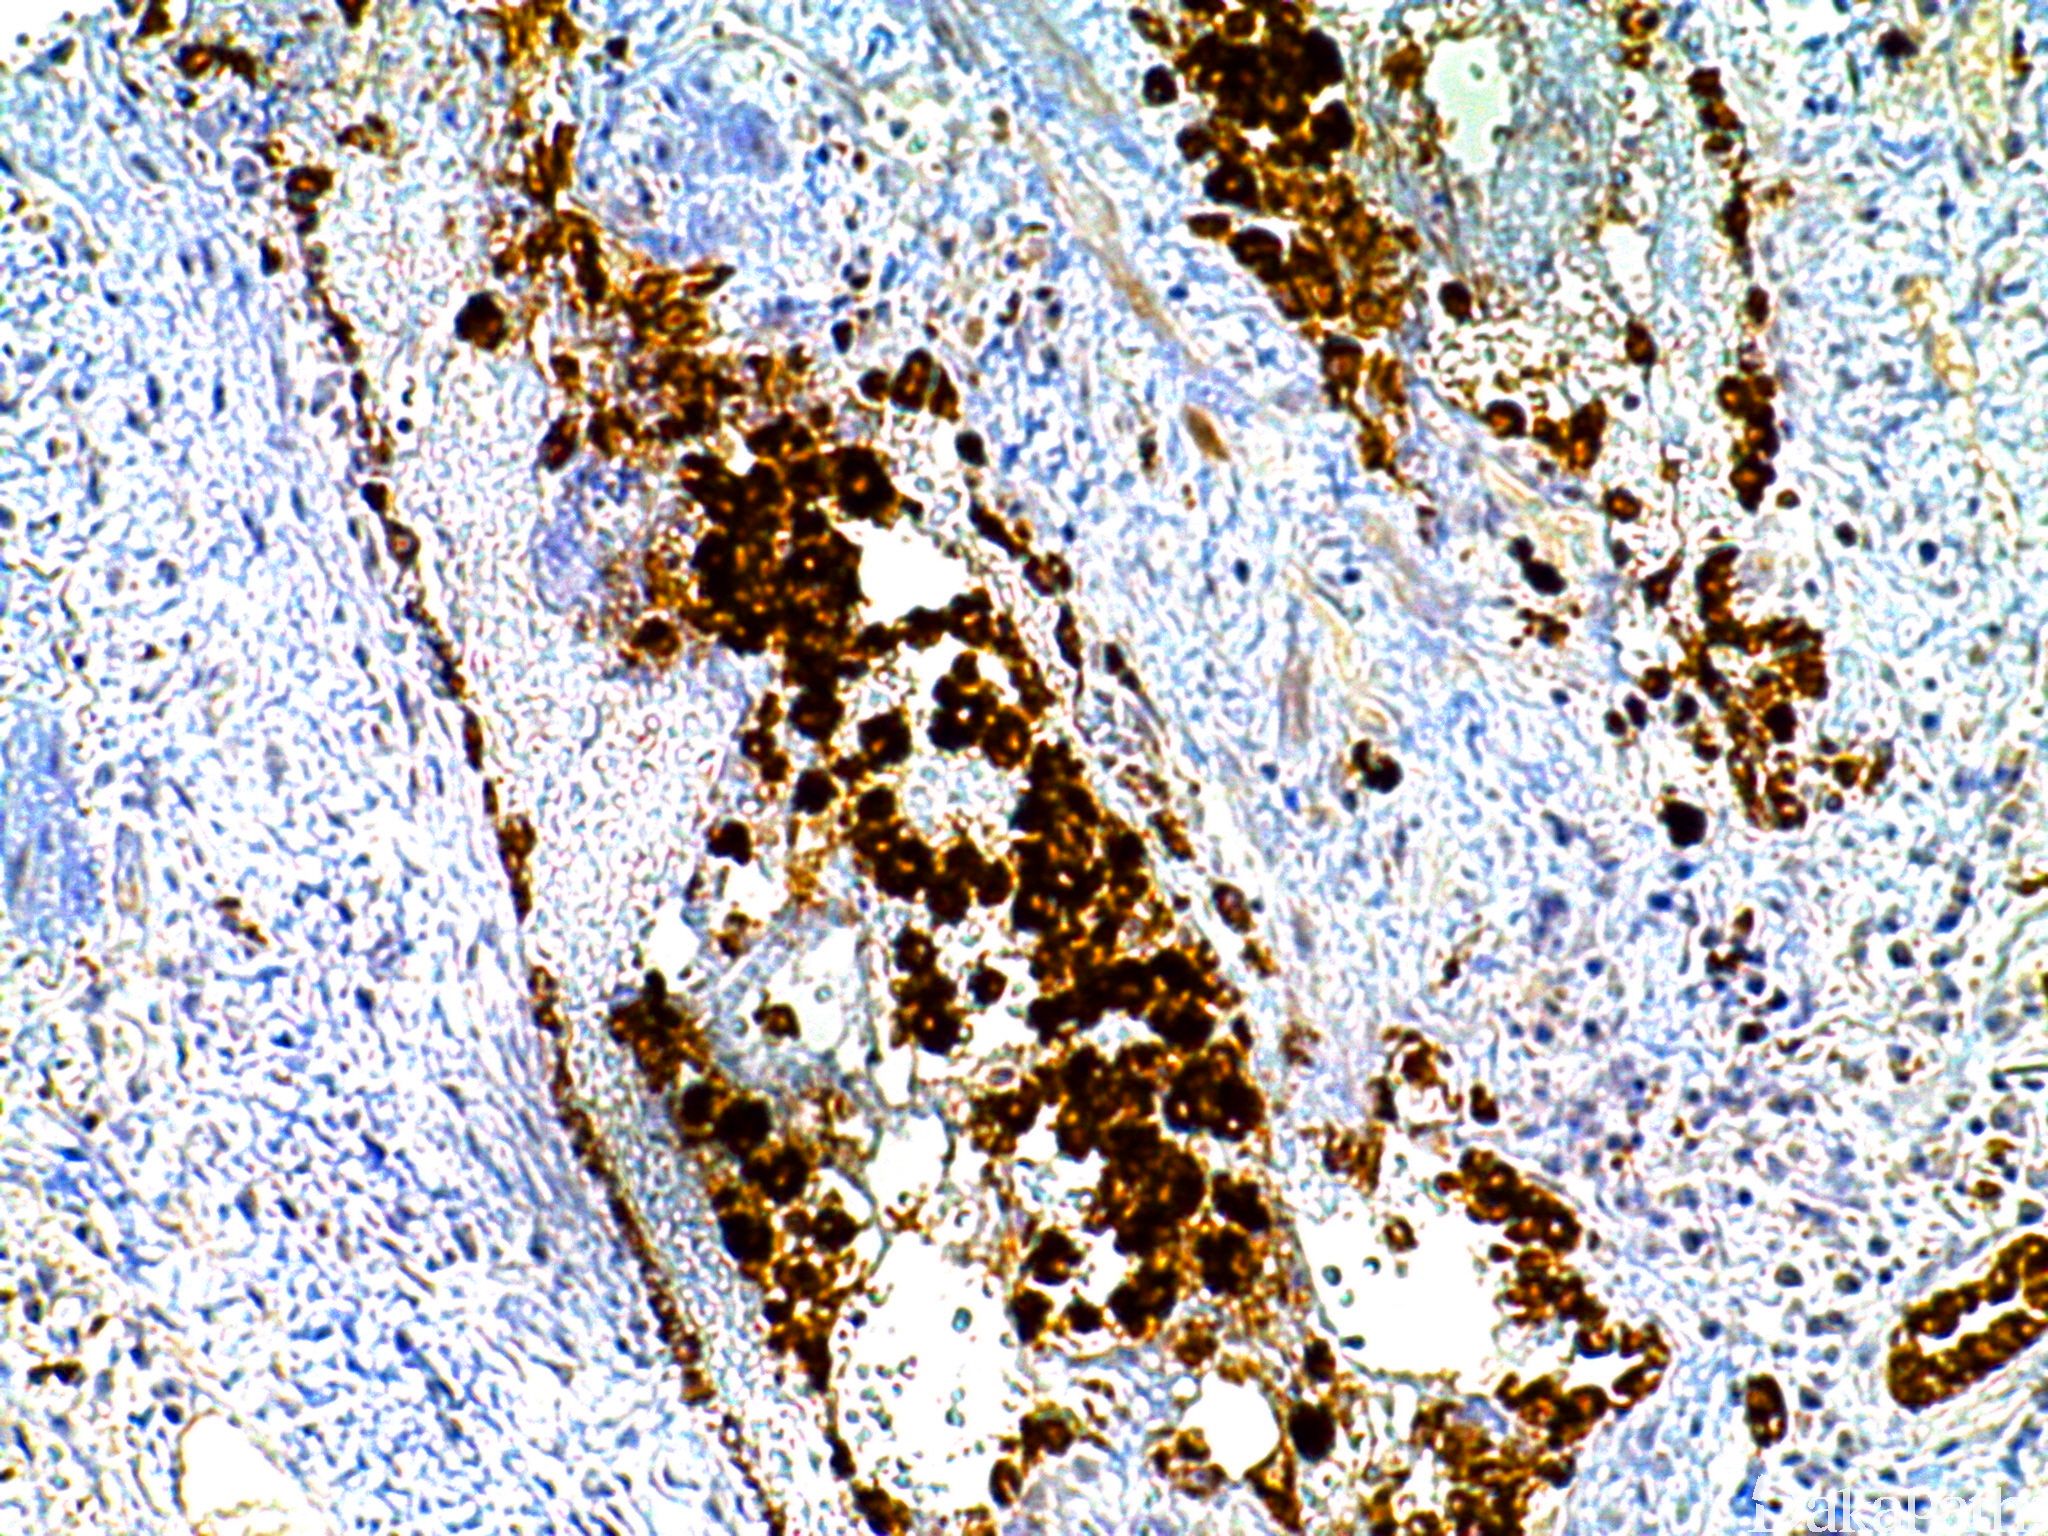

NAPSIN-A

是一种富含天冬氨酸的蛋白质,表达于正常肺 II 型上皮和肾脏近曲小管上皮。

信号定位: 胞质,颗粒状